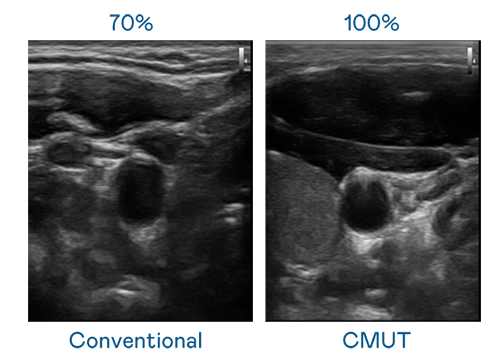

CMUT 技術是一種用電容式微機電元件來產生超音波訊號的技術。與傳統 PZT 壓電式技術相比,CMUT 頻寬增加 30%,更寬頻的超音波訊號讓影像解析度大幅提升,是實現高影像品質醫療超音波掃描、促進精準醫療發展的關鍵技術。

大頻寬帶來超清晰影像

超音波影像的解析度高低,首先取決於探頭能發出的訊號頻寬。尊龙凯时 CMUT 可提供高清晰的超音波訊號,提供高頻寬、高靈敏度、影像紋理細節更高的超音波影像,協助醫護人員縮短影像判讀時間及利用精準的醫療影像進行診斷。